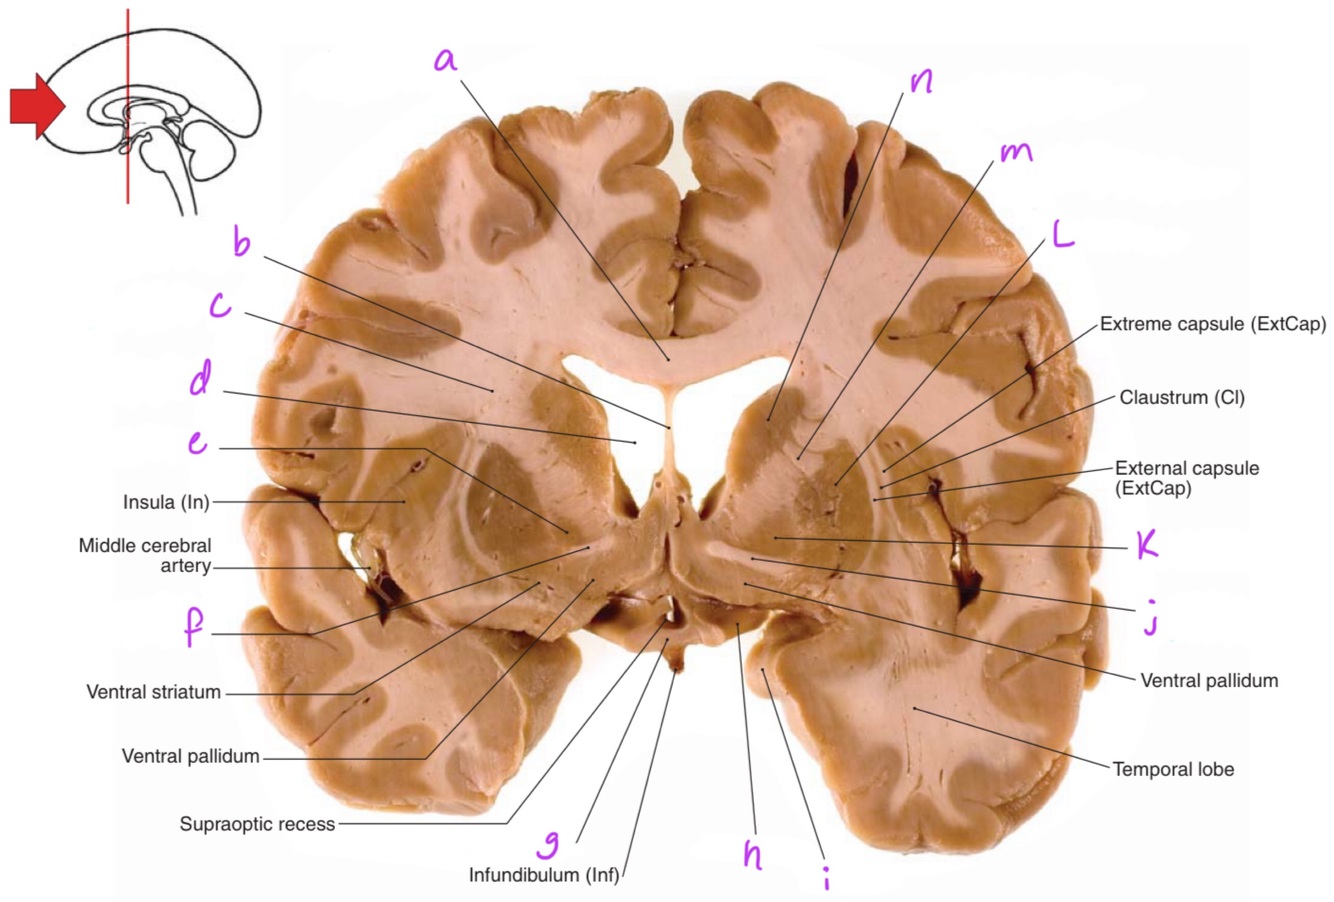

a

body of corpus callosum

b

Anterior horn of lateral ventricle

c

Septum pellucidum

e

Head of caudate nucleus

Q

g

Putamen

1

2

8

h

Nucleus accumbens

11

Corona radiata

12

13

Globus pallidus

14

Anterior commissure

15

Optic chiasm

16

Optic tract

17

Uncus

18

19

20

21

Anterior limb of internal capsule

22